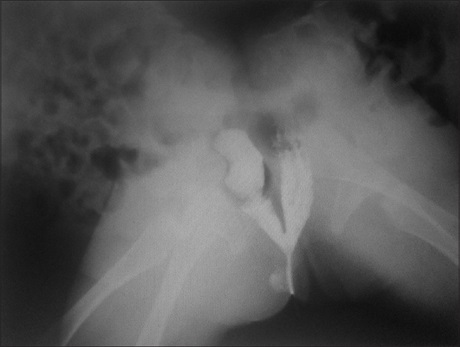

Asymptomatic Unilateral Pulmonary Hypoplasia/Agenesis in Adults: A Report of Six Cases

Prof. Funsho Komolafe, Mohammed Haroun Dahniya, Al-Ali Yesar, Al-Zaabi Lemya, Aziz Fadhil (Author)

99-103